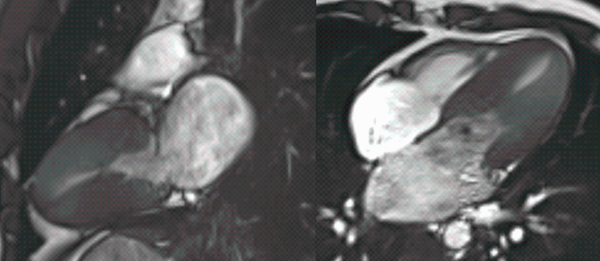

Rare intra-cardiac mass